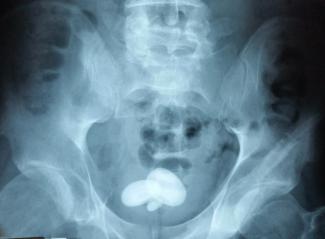

Δεν είναι καθόλου λίγοι αυτοί που πιάνονται κατά καιρούς να μεταφέρουν ναρκωτικά μέσα στο σύστημά τους, κανείς τους πάντως δεν ήταν τόσο ξεροκέφαλος όσο ο τύπος της ιστορίας μας.

Γιατί αυτόν τον έπιασε η αστυνομία, εκείνος αρνούνταν ωστόσο να… καταθέσει τα αποδεικτικά!

«Ο άντρας δεν πιστεύει πως έχουμε τη δύναμη να τον κρατήσουμε μέχρι να αφαιρέσει τα εν λόγω αντικείμενα [ναρκωτικά] από τον πρωκτό του», έγραψε η αστυνομία και ξεκίνησε ένας ακήρυχτος πόλεμος μέσα και έξω από την τουαλέτα του κρατητηρίου. Και όπως ήταν φυσικό, το αστυνομικό τμήμα κρατούσε ενήμερους τους ακολούθους του στο Twitter για την εσκεμμένη δυσκοιλιότητα του υπόπτου, τον οποίο είχαν σταματήσει σε μπλόκο.

Όπως ήταν φυσικό, οι αστυνομικοί ζήτησαν τρεις φορές την παράταση της κράτησής του από τον εισαγγελέα, κάτι που έγινε φυσικά.

Ο ύποπτος αρνούνταν να φάει και να πιει το οτιδήποτε, για ευνόητους λόγους, σύμφωνα πάντως με το αστυνομικό σώμα (Operation Raptor): «παρακολουθείται καθημερινά από γιατρούς, γιατί αυτή είναι η επιλογή του, και η υγεία του είναι καλά».

Εκπρόσωπος της αστυνομίας είπε στο δικαστήριο: «Ο μόνος άνθρωπος που το αποτρέπει αυτό από το να συμβεί είναι ο ίδιος ο κατηγορούμενος». Η παράδοξη αυτή μάχη αστυνομίας και υπόπτου έγινε ανάρπαστη όπως ήταν φυσικό στο Twitter, καθώς οι αστυνομικοί εξάντλησαν το χιούμορ τους στα hashtags (#WeWontGiveUp, #ComeOn, #MustBeHungry και #HowLongCanYouGo), αν και η υπόθεση ήταν και για γέλια και για κλάματα.

Ο 33χρονος Aaron Hudson προδόθηκε τελικά από τον οργανισμό του στην απίστευτη πραγματικά 27η μέρα και πιάστηκε με ποσότητα ναρκωτικών. Όπως δήλωσε χαρακτηριστικά ο διοικητής του τμήματος του αγγλικού Σάσεξ: «Αυτό πρέπει να λειτουργήσει ως υπόμνηση σε κάθε διακινητή που προμηθεύει ναρκωτικά το Σάσεξ πως θα χρησιμοποιήσουμε κάθε ‘‘παραθυράκι’’ του νόμου ώστε να σε κυνηγήσουμε»…